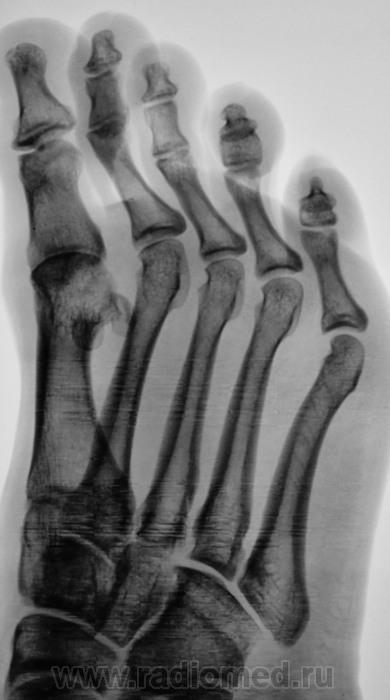

Пол пациента: Женский пол Тип патологии: Другое Область исследования: Скелетно-мышечная система Методы исследования: Rg Боли в стопе. Направлен на рентгенографию стопы. https://radiomed.ru/sites/default/files/styles/case_slider_image/public/user/12/2.201201010085.jpg?itok=dJXkcu51 https://radiomed.ru/sites/default/files/styles/case_slider_image/public/user/12/3.201401050084.jpg?itok=IXpYjiPy https://radiomed.ru/sites/default/files/styles/case_slider_image/public/user/12/4.201401050086.jpg?itok=HhXvQ302 ID:34659 Чт, 09/01/2014 - 19:39 #1 Сергей Кузьминов Не на сайте Был на сайте: 1 год 2 недели назад Зарегистрирован: 06.10.2012 - 15:51 Публикации: 11813 Назову неполным вывихом в первом плюстнефаланговом суставе. Чт, 09/01/2014 - 19:41 #2 pumpan86 Не на сайте Был на сайте: 9 лет 12 месяцев назад Зарегистрирован: 03.01.2012 - 10:49 Публикации: 60 Сергей Кузьминов wrote: Назову неполным вывихом в первом плюстнефаланговом суставе. +1. Он же подвывих.

Назову неполным вывихом в первом плюстнефаланговом суставе.